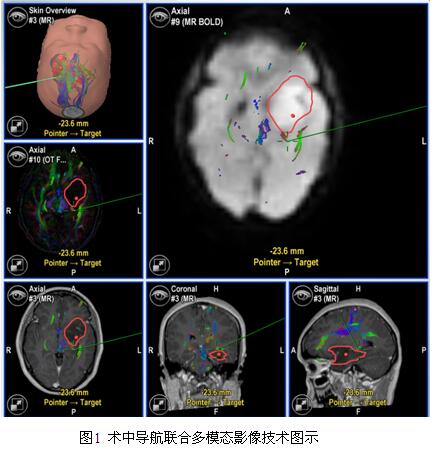

2.病例处理 所有病例均已行开颅切除肿瘤,术前均行MRI平扫增强检测,功能区及功能区附近病变均已行DTI检查,部分病变行MRS、fMRI及脑灌注检查。根据术前影像资料及相关临床数据进行评估,功能区及功能区附近病变符合唤醒条件的经与患者及其家属充分沟通后,行唤醒手术;唤醒麻醉下共切除肿瘤16例,非唤醒麻醉下切除肿瘤31例。所有病例行术中导航联合多模态影像技术(图1),部分病例还运用了术中荧光、术中B超等手段。术后48小时内均已行MRI平扫及增强检查。

3. T2Flair术前、术后及切除范围计算方法 收集患者术前、术后48小时内MRI-Flair图像,术前、术后MRI图像导入德国Brainlab计划系统,采用Brainlab-iPlan软件定量计算术前、术后残余T2Flair体积(如图1a),并计算出T2flair 切除程度。